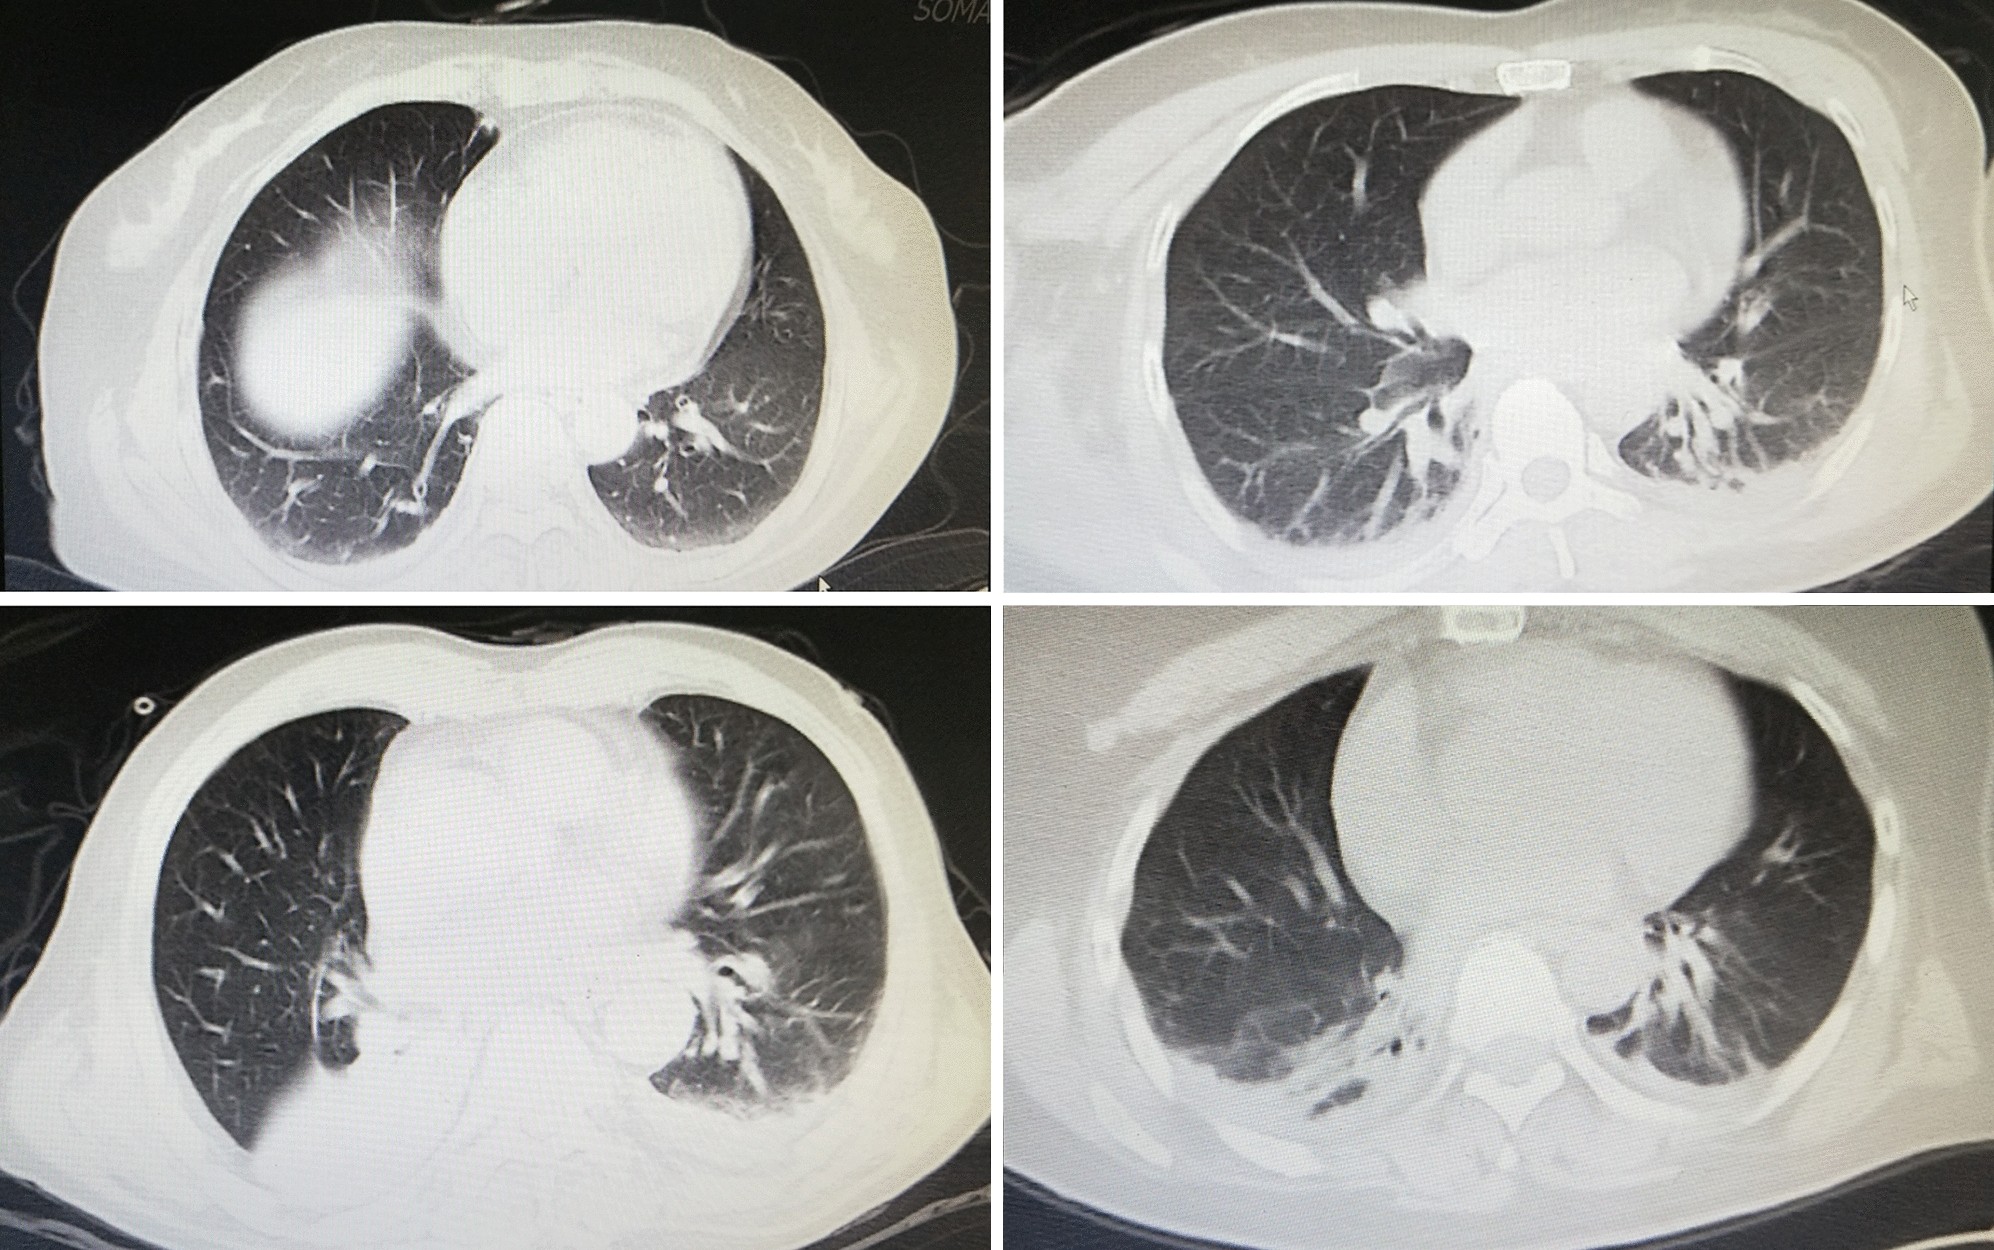

Figure 1

The first postoperative chest CT image showed bilateral pulmonary imaging abnormalities after craniotomy of brain tumor.